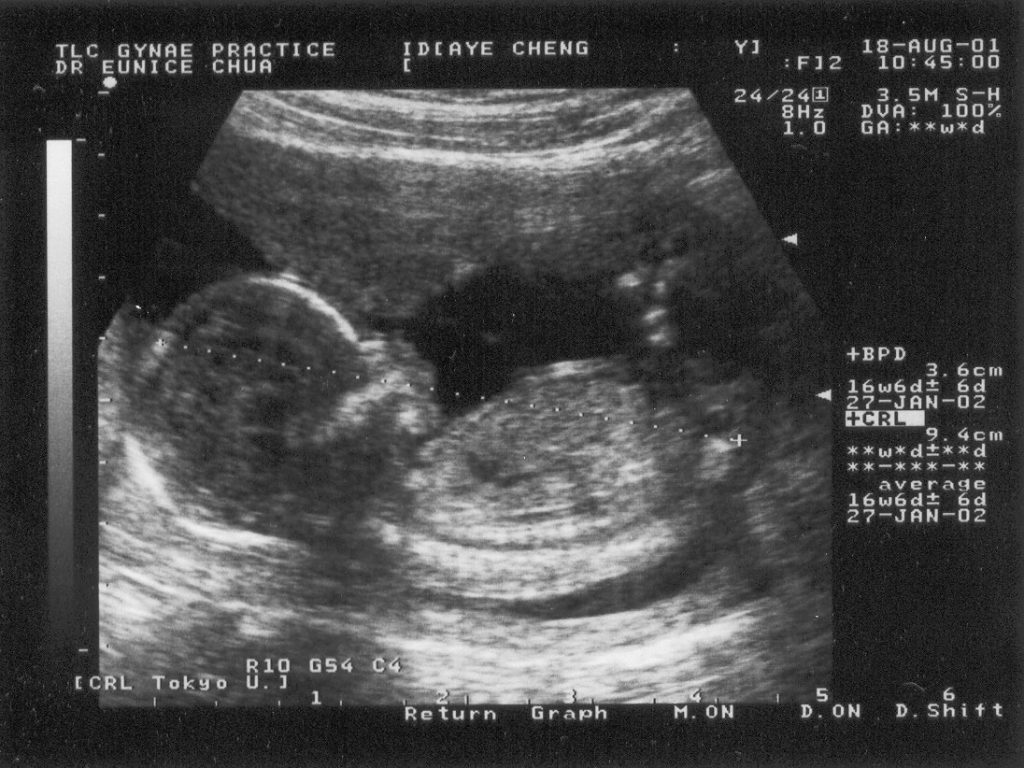

- Medical imaging: To examine internal tissues, organs of a patient, development of unborn baby (foetus). Ultrasound allows imaging because of the difference in time taken for the waves to return from different depths of the medium. Computers constructs images of tissues/organs/foetuses from reflected ultrasonic signals.

An example of an ultrasound scan of a foetus.

An example of an ultrasound scan of a foetus.

Understand that the image should not be thought of as a photograph,

but rather a cross-section through the patient.